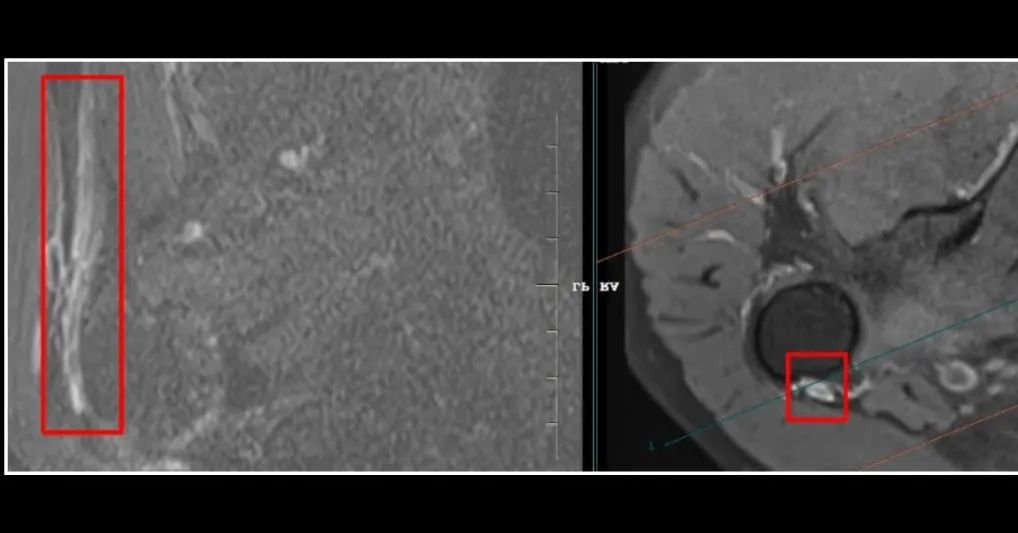

Empty bicipital groove with bursal fluid collection and non-visualisation of long head of biceps tendon within the groove – *suggestive of long head of biceps tendon tear with distal retraction (the retracted portion of the tendon is not imaged in this study*).

long head of biceps tendon tear with distal retraction (the retracted portion of the tendon is not imaged in this study).